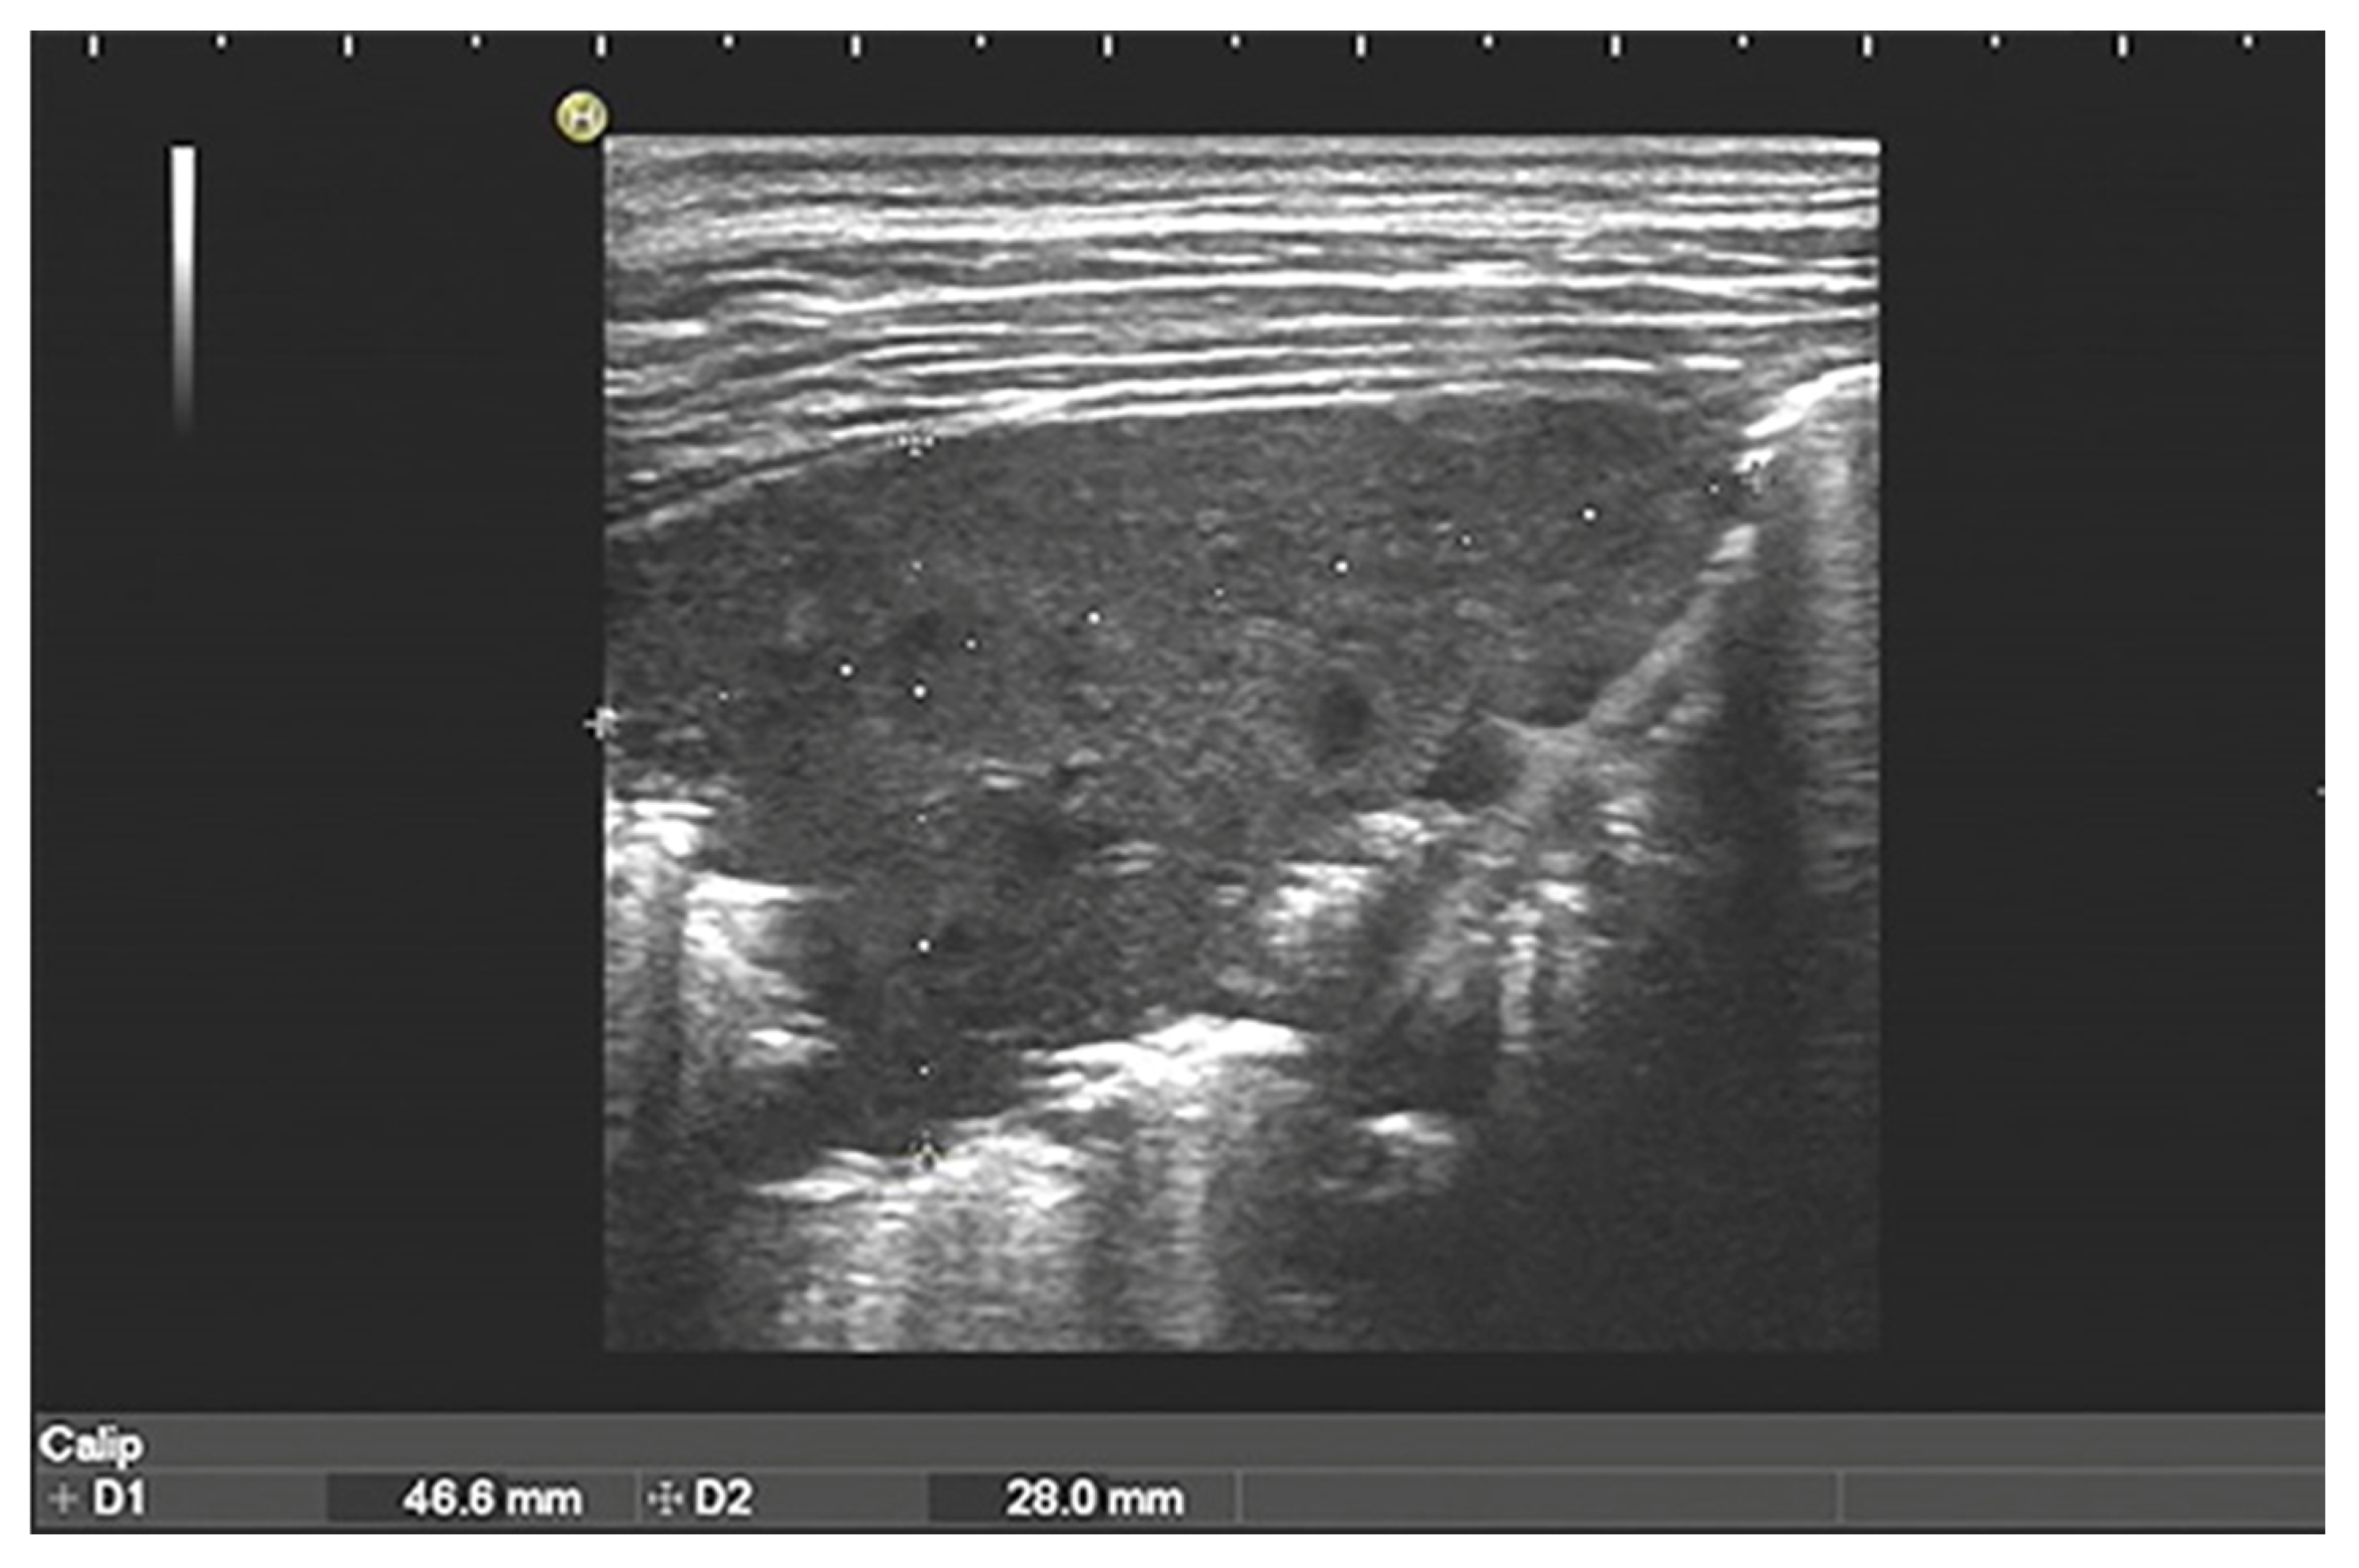

- Meli, M.; La Spina, M.; Lo Nigro, L.; Trobia, G.L.; Russo, G.; Di Cataldo, A. Pleuro-pulmonary ultrasound in the diagnosis and follow-up of lung infections in children with cancer: A pilot study. J. Ultrasound 2022, 25, 865–875. [Google Scholar] [CrossRef]